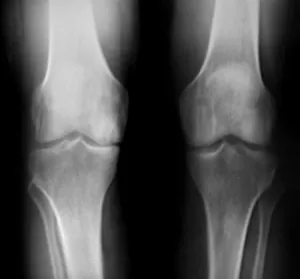

Diagnosis typically begins with a medical history and physical exam. Imaging may include:

• X-rays, to evaluate bone changes and rule out other knee conditions

knee osteoarth diagnosis02